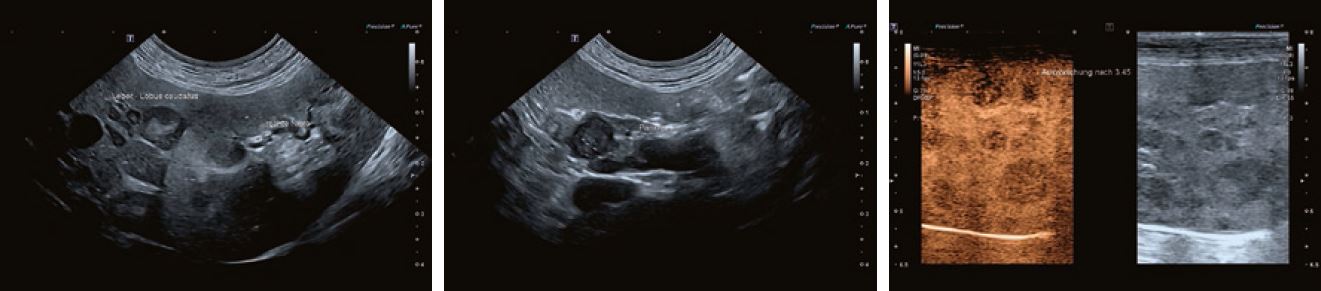

Випадок 2

Цуценя з гнійним животом через абсцес пупка - на фото.

Випадок 3

Йоркширський Тер'єр з гематурією через новоутворення вентральної стінки сечового міхура.

Французький бульдог, десятирічний; поступив з хронічною блювотою і втратою ваги; біохімія крові в нормі, лейкоцити низькі (2400); УЗД з різко гіпоехогенними, неправильної форми ураженнями в печінці і головці підшлункової залози, круглим вогнищем в області правого наднирника; CEUS 2,5 мл Sonoview, датчик 11L3 вимивання уражень печінки через 3,45 хв, на жаль, підсилення надто високе, але все ще діагностоване; евтаназія через два місяці